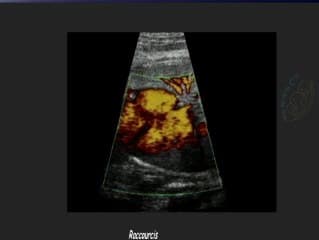

Comme à son habitude Jérôme LEBIDOIS nous montre de très belles images et vidéos très didactiques de cardiopathies : sténose aortique, VDDI, TGV, tétralogie de Fallot, APSO. A voir et à revoir pour ne pas les rater...